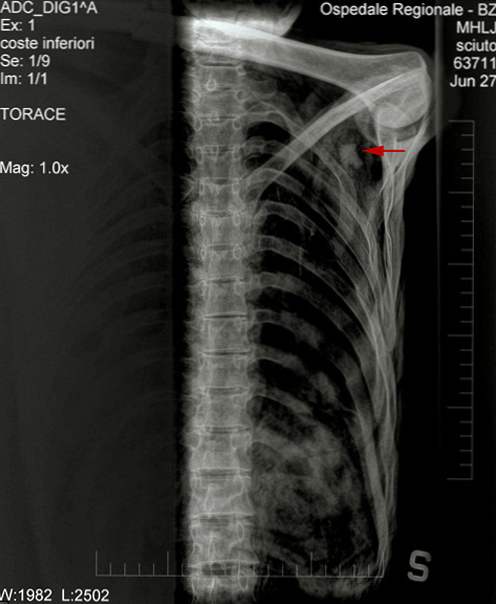

Глибоко в плечі Етці був знайдений наконечник стріли.